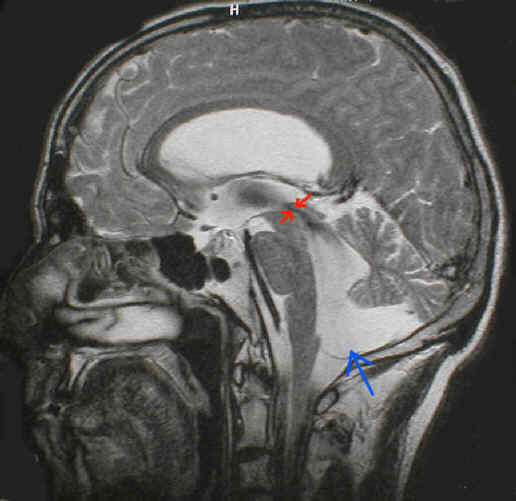

Die Abbildung zeigt eine Aquäduktstenose im oberen Drittel des Aquädukts (rote Pfeile), sowie eine Dandy-Walker-Variante (blauer Pfeil).

Eine Veränderung die isoliert oder in Kombination mit anderen Mißbildungen vorkommen kann. Insbesondere sehr häufig bei offenem Rückenmark (Spina bifida / Meningomyelocele). Das charakteristische daran ist, dass die hintere Schädelgrube, in der normalerweise das Kleinhirn und das Stammhirn liegen quasi zu klein ist für diese Hirnanteile. Aus diesem Grund verlagern sich diese Hirnanteile nach unten in den oberen Rückenmarkskanal. Das Bild oben zeigt mit der blauen Linie das Niveau an auf dem die hintere Schädelgrube nach unten hin endet. Unschwer ist zu erkennen, dass Anteile des Kleinhirns (rot umrandet) und Anteile des Stammhirns (gelb umrandet) dieses Niveau deutlich unterschreiten. Zusätzlich besteht eine Aquäduktstenose (grüne Pfeile). Die Kombination von Chiari-Mißbildung und Aquäduktstenose ist gar nicht selten anzutreffen, denn durch die Enge in der hinteren Schädelgrube wird der obere Kleinhirnanteil auch häufig nach oben in Richtung des Großhirns verschoben. Da die anatomische Begrenzung der hinteren Schädelgrube zum Großhirn hin (das Tentorium) typischerweise auch häufig sehr schwach ausgebildet ist, wird diese Verlagerung des Kleinhirnes auch noch gefördert. Durch die Verlagerung von Kleinhirnanteilen nach oben wird das Mittelhirn gequetscht und in ihm liegt der Aquädukt, der dabei ebenfalls gequetscht wird.